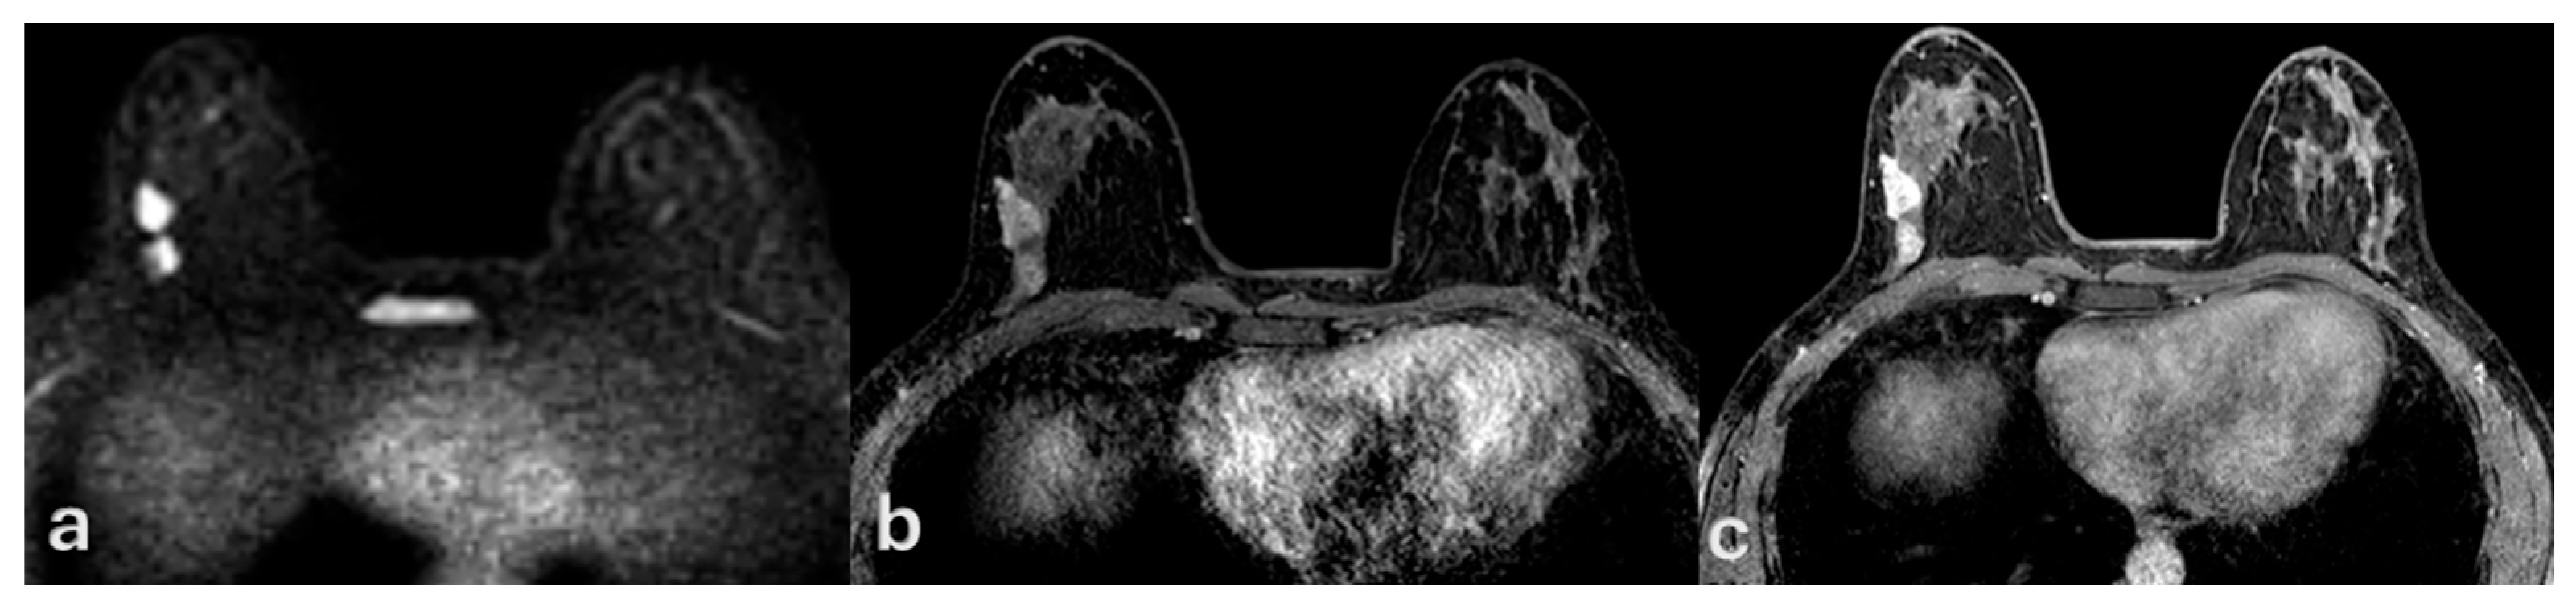

- Nadrljanski, M.M.; Marković, B.B.; Milošević, Z. Breast ductal carcinoma in situ: Morphologic and kinetic MRI findings. Iran. J. Radiol. 2013, 10, 99–102. [Google Scholar] [CrossRef] [PubMed]

- Chan, S.; Chen, J.H.; Agrawal, G.; Lin, M.; Mehta, R.S.; Carpenter, P.M.; Nalcioglu, O.; Su, M.Y. Characterization of Pure Ductal Carcinoma In Situ on Dynamic Contrast-Enhanced MR Imaging: Do Nonhigh Grade and High Grade Show Different Imaging Features? J. Oncol. 2010, 2010, 431341. [Google Scholar] [CrossRef]

- Agrawal, G.; Su, M.Y.; Nalcioglu, O.; Feig, S.A.; Chen, J.H. Significance of breast lesion descriptors in the ACR BI-RADS MRI lexicon. Cancer 2009, 115, 1363–1380. [Google Scholar] [CrossRef]